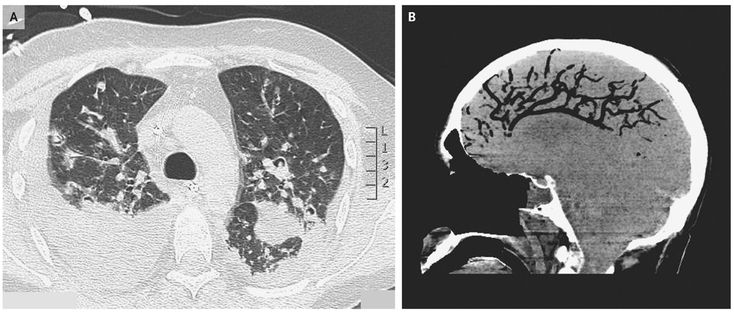

A 42-year-old man had acute respiratory failure after receiving all-trans retinoic acid for the treatment of acute promyelocytic leukemia. Computed tomography (CT) of the chest revealed multiple nodular lesions (Panel A), which on biopsy showed invasive aspergillus species. The patient was treated with antifungal therapy and received mechanical ventilation. His clinical condition was improving when he had an episode of sudden and severe hemoptysis, followed by cardiac arrest. He was resuscitated, but subsequently a severe neurologic deficit developed. A brain CT scan revealed cerebral air embolism, especially in the anterior arterial-circulation territory, with accompanying cerebral edema (Panel B). Cerebral air embolism can be caused by positive-pressure maneuvers performed during cardiac resuscitation, lung biopsy, and the placement of venous catheters in the presence of a patent foramen ovale. Lung biopsy was not performed in this patient, and venous catheters were already in place. Cardiac resuscitation maneuvers were the likely cause of the condition in this patient. Diffuse cerebral edema developed, and the patient was declared brain dead on the fifth day after diagnosis.